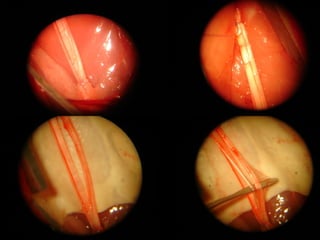

Neurorrafia y Neurolisis

Neurorrafia

Injerto de nervio